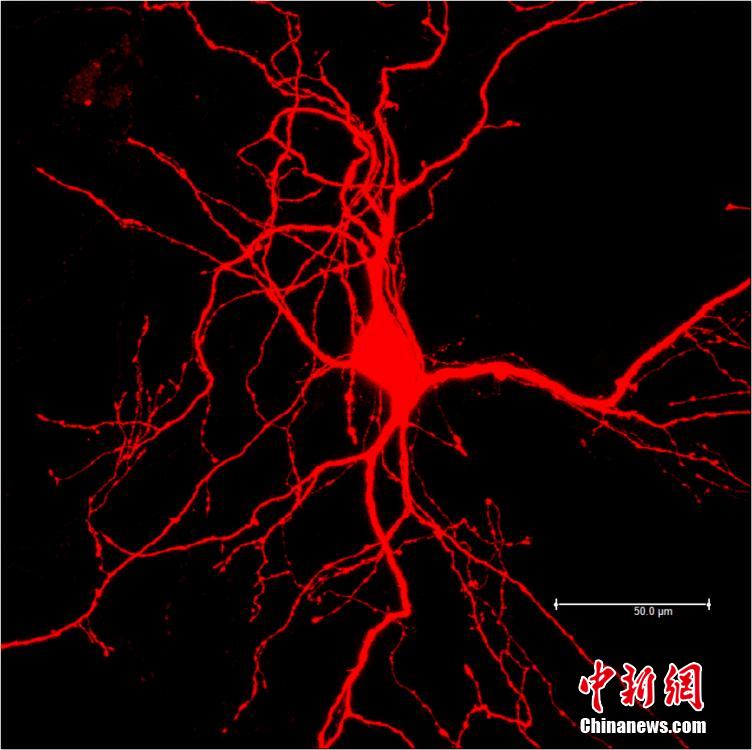

神经元细胞染色。神经元细胞,由神经元核心向四周发散,如章鱼触角,触角上分布一个个小凸起的触发器,生物电流在上面传到,起到信息传导指挥的作用(显微镜放大1200倍)。钟欣 摄